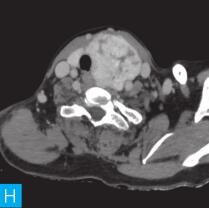

甲状腺CT检查:CT检查设备为256层iCT,病人采取仰卧位,扫描范围自外耳道平面至下颌角以下,常规扫描层厚为0.9mm、层间隔0.9mm,电压120kV,管电流280mA,矩阵512×512;经右肘静脉团注法增强扫描,碘海醇80ml,流速4ml/s,动脉期25秒扫描,静脉期60秒扫描。见图1。

图1 甲状腺CT

A、B.甲状腺CT横断面平扫;C~H.甲状腺CT横断面增强

答案A 解析:甲状腺左叶病变边界清楚,形态较规则,密度不均匀,部分为实性改变,部分为囊性灶,其内可见斑点状粗大钙化灶,气管及食管向右推移,左侧颈总动脉向左后推移,胸锁乳突肌向左前推移。根据表现病变不是单纯囊性病变。

答案C 解析:该病灶病史时间长,无发热及疼痛;病变位于一侧甲状腺,边界清楚;甲状腺血流及静态显像示:甲状腺左叶较大“凉”结节。因此不考虑恶性肿瘤及感染性病变。病变强化特点为结节状改变,呈现肿块样,故考虑肿瘤样病变。

CT平扫可见甲状腺左叶圆形以低密度为主病灶,大小为8.0cm×6.5cm,边界清晰,边缘尚光整,其内密度不均匀,低密度区CT值18HU,部分密度稍高,并可见斑点状粗大钙化影;CT增强后,甲状腺左叶病变呈不均匀渐进性强化,结节状改变,动脉期强化区CT值99HU,静脉期CT值85HU,且强化范围增大,提示该病变的血供较为丰富,应该考虑肿瘤样病变,结节性甲状腺肿可能性大。

本病例CT扫描发现起源于甲状腺较为容易,但要观察病变是囊性、实质性或囊实性及其供血,CT增强扫描十分必要,易于显示囊实性病变及其供血情况,其结节状改变更加显著,有助于判定病灶的血液供应情况。本病例基本征象为类圆形、边缘清晰、内粗大钙化、结节状强化之肿块。

多见于桥本甲状腺炎病人,短期内肿块迅速增大,CT平扫及增强密度多较均匀,强化程度呈轻中度,周围血管呈包绕而非推移样表现,较大瘤体常向气管食管沟延伸(见图1)。

该例病变位于甲状腺左叶,左叶不对称性增大,其内多发散在不规则强化结节影,斑点状粗大钙化,钙化周围可见星状伪影,提示钙化为长期慢性形成,而且钙化比较致密。肿块虽然很大,但与邻近气管、食管及血管等无明显侵犯或浸润征象。病变内部可见多发囊变区,增强检查实性部分呈明显均匀强化,包膜完整。双侧锁骨上区未见肿大淋巴结。提示病变为良性。病变多发,伴囊变、钙化,临床为中老年女性病人,颈前无痛性肿物。结节性甲状腺肿诊断明确。结节性甲状腺肿常常较大,术前影像学的评估包括:①病变的范围,累及胸骨下的范围决定手术治疗的方式,手术是否需要打开胸骨;②病变与气管的关系,是否具有气管软化,如果存在气管软化,要提醒临床医生手术过程中以及术后出现呼吸困难;③注意是否合并甲状腺癌,尤其是乳头状癌。要仔细寻找包膜是否完整,内部有无微小的乳头,以及邻近Ⅵ区或Ⅳ区是否伴有淋巴结转移。